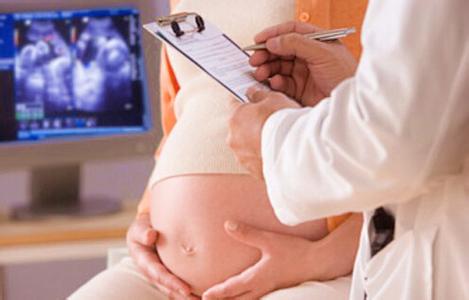

这次产检是孕晚期的常规检查,了解孕妈咪的健康状况以及胎儿在宫内的发育情况,为足月后的分娩做准备。

孕37周开始,接下来的4周里,孕妈每周都需要进行产检。常规检查的项目包括血压、体重、宫底高度、腹围、胎位、血常规、尿常规等。并且32周以后,每一次产检都会加入胎心监护,每次要做20分钟,通过这项检查来了解胎宝宝在子宫内是否缺氧的情况。